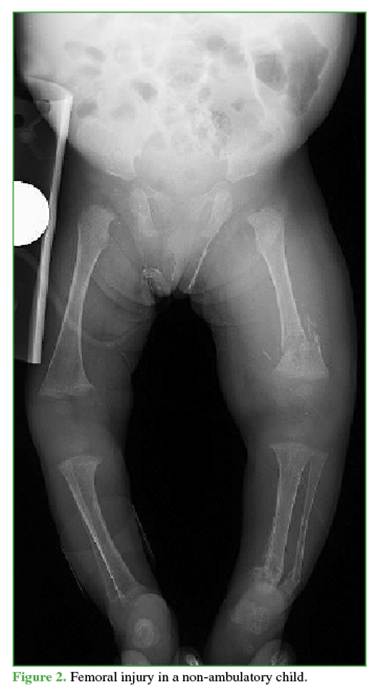

4.     Femoral fractures due to abuse are more likely in children who are not yet walking (Figure 2).